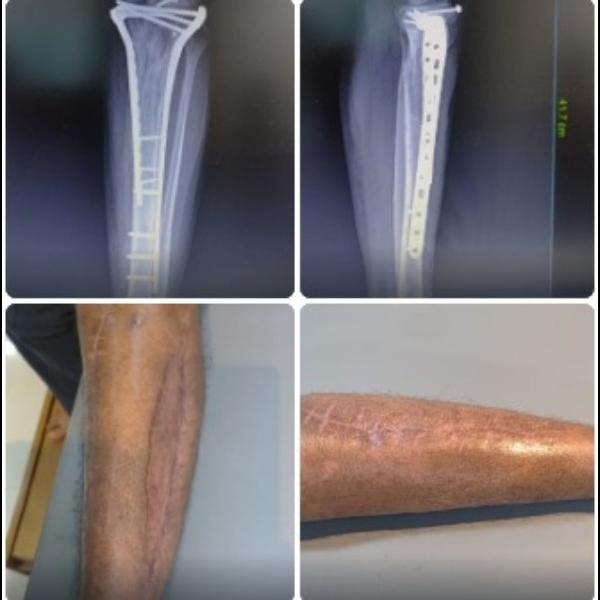

Fracture of Distal end Tibia and Fibula Fixation